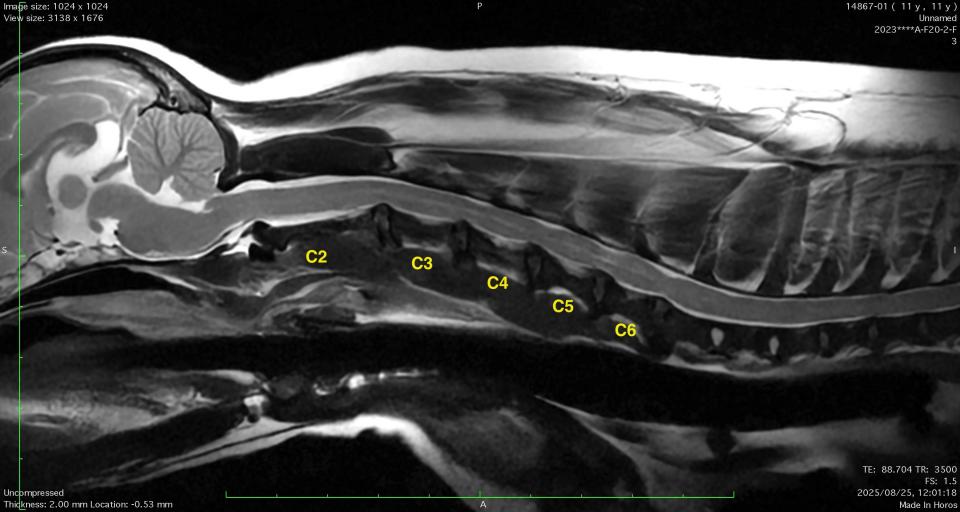

C2-3-4-5-6椎間において多発性椎間板ヘルニアが認められました。

MRI検査のみでは多発性椎間板ヘルニアにおける責任病変の特定が困難な場合があり、脊髄動的圧迫は評価できません。